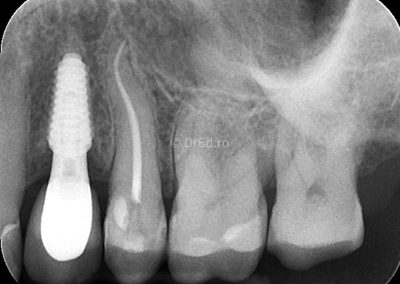

Galerie

Toate imaginile, fotografiile și radiografiile publicate pe acest site sunt protejate prin drepturi de autor și constituie proprietatea exclusivă a Dred.ro.

Aceste materiale sunt furnizate exclusiv în scop informativ și educațional și nu conțin date cu caracter personal sau informații care permit identificarea pacienților, în concordanță cu legislația privind protecția datelor cu caracter personal și GDPR.

Reproducerea, copierea, distribuirea, publicarea, transmiterea, modificarea sau orice altă utilizare, integrală ori parțială, a acestor materiale, în orice formă și prin orice mijloace, fără consimțământul prealabil scris al titularului drepturilor, este strict interzisă și poate atrage răspunderea civilă și/sau penală, în condițiile legii aplicabile privind drepturile de autor și protecția proprietății intelectuale.